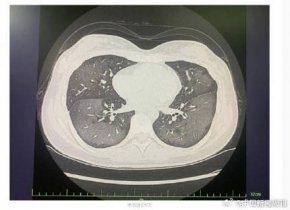

盛吉芳称,当炎性渗出达到一定程度,拍片时肺组织就会呈现成片的白色,但是造成“白肺”情况有很多种,感染新冠只是其中的一种可能。盛吉芳表示,市民若出现持续高热不退、剧烈咳嗽,并伴有持续胸闷、胸痛等症状,建议及时就医。

据中国人民解放军总医院呼吸与危重症医学部主任医师解立新介绍,“白肺”就是一些液体或者是一些体外的异物进入肺泡腔,把肺泡腔充满,然后我们通过X线或CT看到,肺呈一个白色的表现,叫做白肺。医生提醒,患者如果出现明显的咳嗽、咳痰、发热,并且病情在逐渐进展,尤其是出现了胸闷气短的表现,要及时到医院就诊。